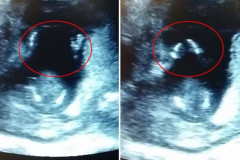

Փոքրիկը մոր արգանդում մայրիկի երգի տակ ծափ է տալիս (տեսանյութ)